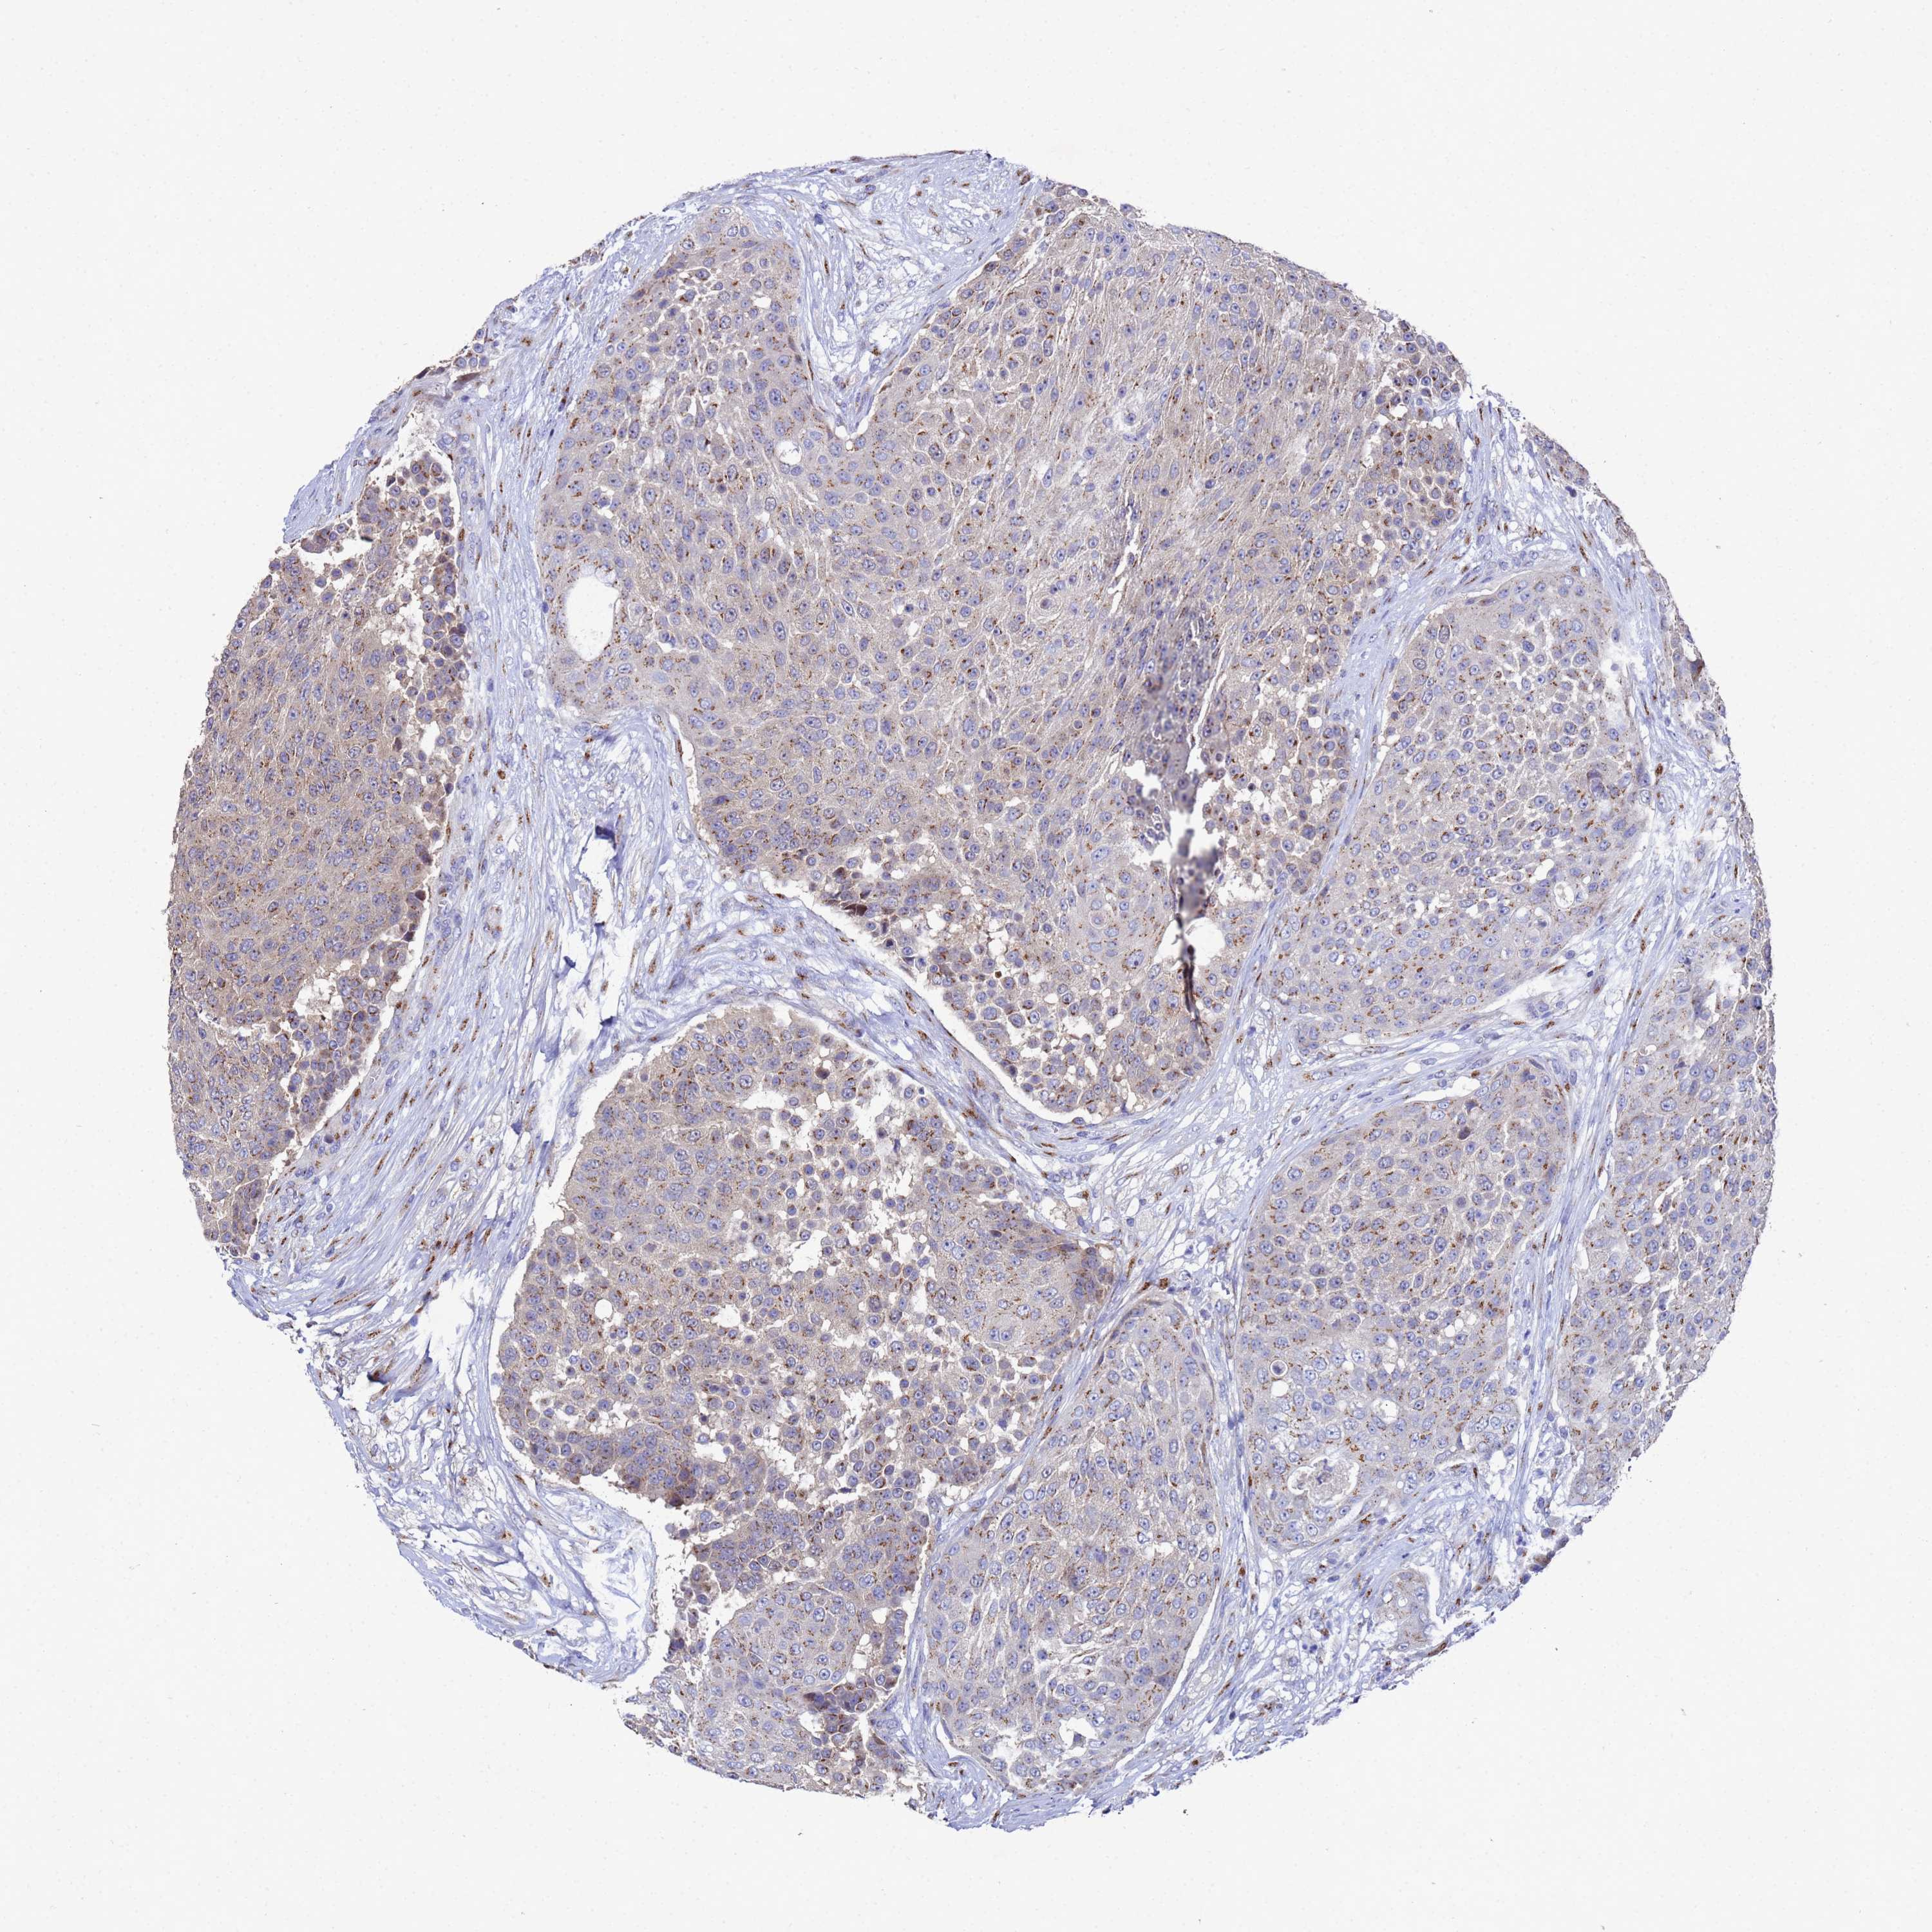

UROTHELIAL CANCER - Protein expressioni

A mouse-over function shows sample information and annotation data. Click on an image to view it in a full screen mode. Samples can be filtered based on level of antibody staining by selecting one or several of the following categories: high, medium, low and not detected. The assay and annotation is described here.

Note that samples used for immunohistochemistry by the Human Protein Atlas do not correspond to samples in the TCGA dataset.

Antibody stainingi

Antibody staining in the annotated cell types in the current human tissue is reported as not detected, low, medium, or high, based on conventional immunohistochemistry profiling in selected tissues. This score is based on the combination of the staining intensity and fraction of stained cells.

Each image is clickable and will lead to virtual microscopy that enables deeper exploration of all samples and also displays staining intensity scores, fraction scores and subcellular localization as well as patient and tissue information for each sample.

Antibody HPA045902

Staining

High

Medium

Low

Not detected

Intensity

Strong

Moderate

Weak

Negative

Quantity

>75%

75%-25%

<25%

None

Location

Nuclear

Cytoplasmic/membranous

Cytoplasmic/membranous,nuclear

Urothelial carcinoma, High grade

Urothelial carcinoma, Low grade